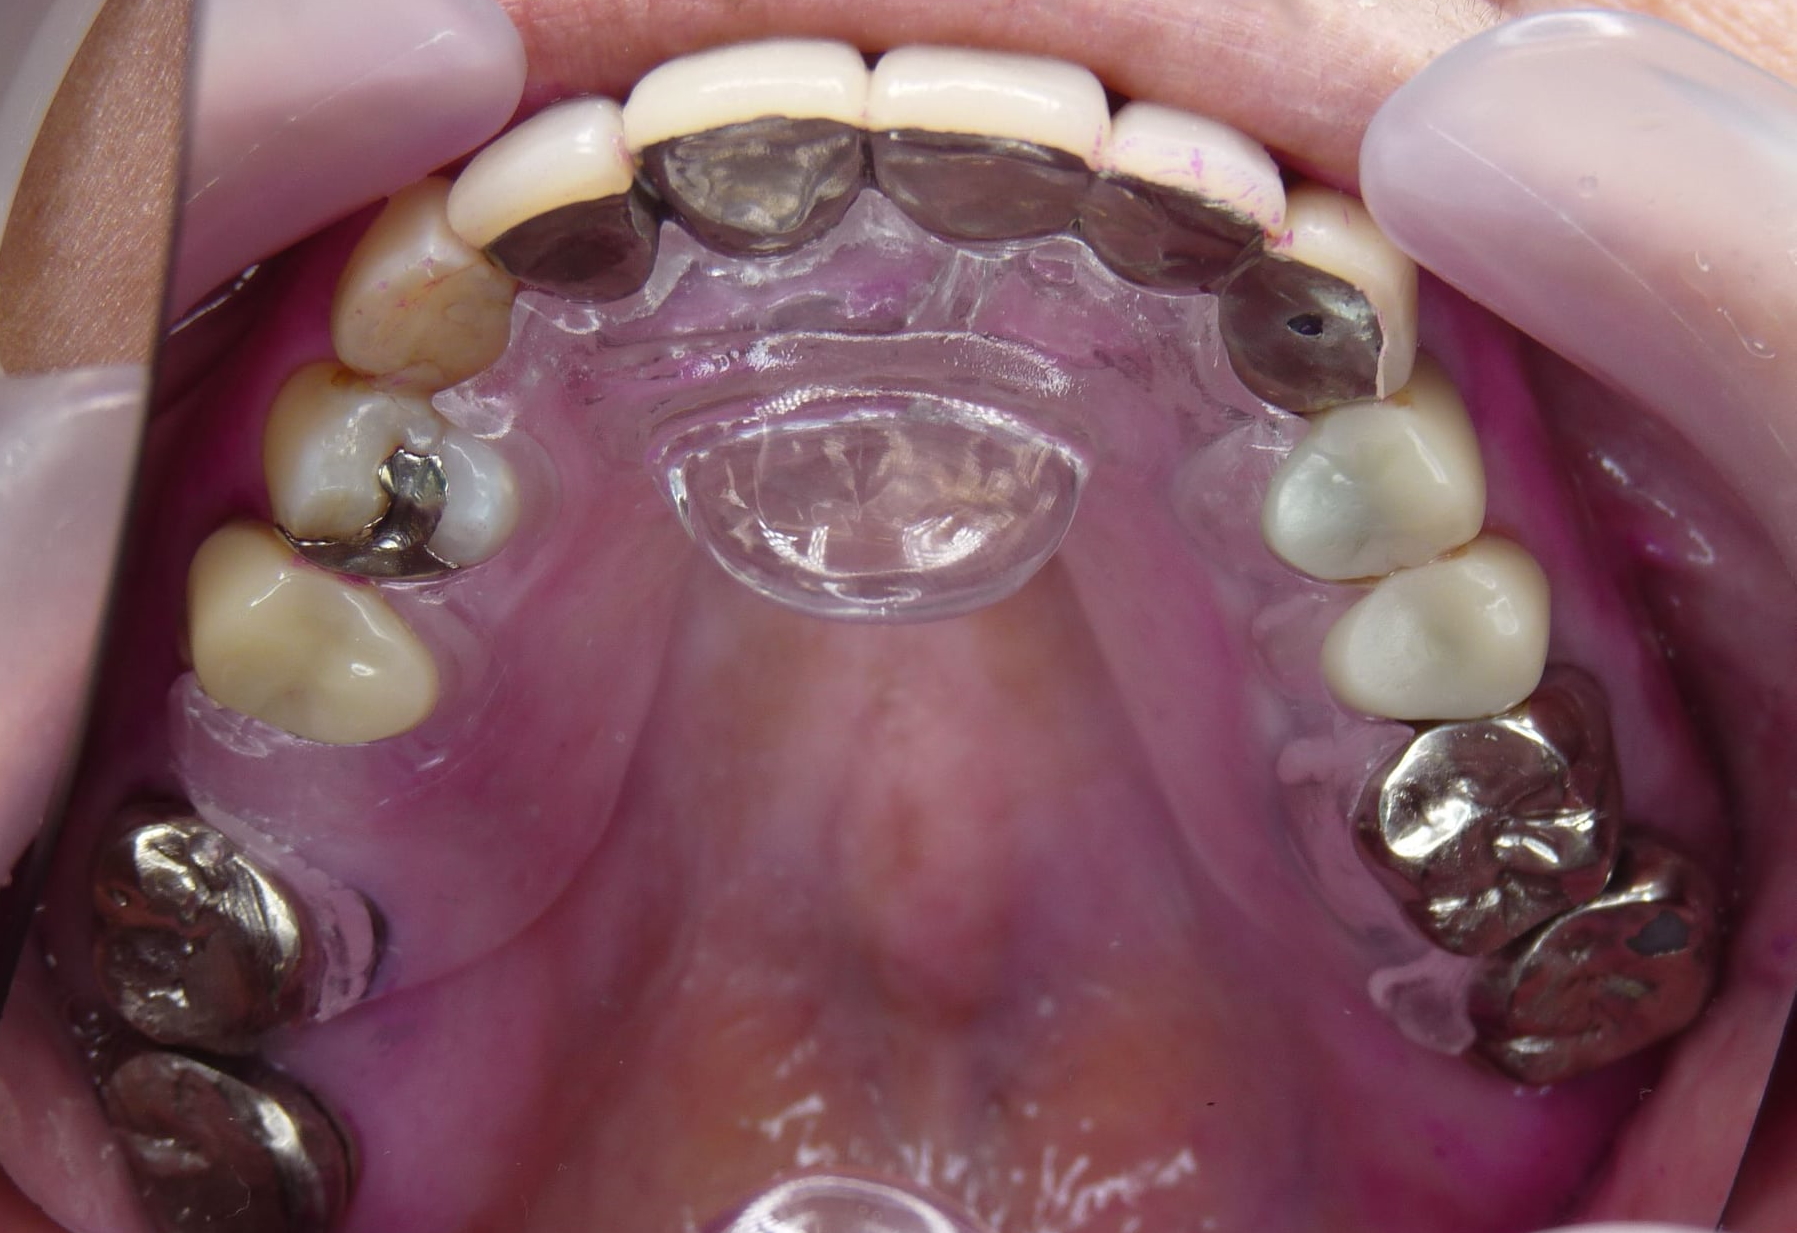

(2019/4/1追加) 最近のTPC 突起が長くなってきました

透明だと探す時に困るという訴えで義歯用加熱重合レジンで作ったもの

このたび義歯床用アクリリック樹脂(加熱重合レジン)を用いて義歯と同じく埋没法で作るように変更しました

外形などは全く変更ありませんので、ワックスアップしてから石膏で埋没します

割り出し以降は変わりません

技工作業をシンプルにするために色付けはせず透明です

作業模型を割らずに割り出した方が後の調整は楽です